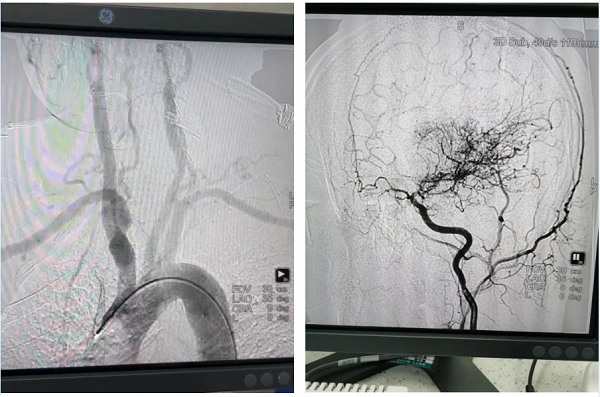

病例:患者男性,67岁,诊断“脑梗死、高血压、糖尿病、冠心病”,颈动脉彩超提示左侧颈动脉起始段狭窄,为进一步明确脑血管情况,预行脑血管造影;患者同时合并冠心病,提出希望能在脑血管造影同时,同台行冠脉造影明确心脏血管情况;为满足患者需求,我院神经内科立即请心血管内科医师会诊评估,最后决定为患者同台行冠脉及脑血管造影,造影顺利完成,精准评估了患者心脑血管狭窄程度,制定后期治疗计划,造影耗时约1.5小时,患者及家属非常满意。

心脏与脑血管造影手术是一种先进的影像学检查技术,通过向血管内注入造影剂,使心脏和脑血管显影,从而动态清晰地显示血管的形态、结构和血流情况。这种技术对于诊断血管狭窄、阻塞、动脉瘤等病变具有重要意义,并为后续的治疗提供精确的指导。

脑血管支架治疗